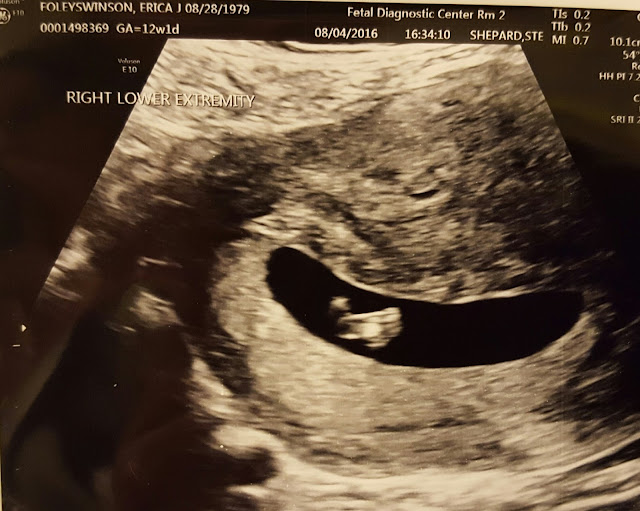

Several weeks ago, Husbeast and I went in for our 18-ish

week ultrasound. Squall looked normal; nuchal translucency was within normal

parameters; we verified that yes, he is indeed a boy, and we found all ten fingers

and toes. What we also found was that Squall’s umbilical cord is one artery shy

of the norm. Babies are supposed to have two arteries and one vein in the

umbilicus. The doctor said that his heart looked great though, and he was

growing a little ahead of the expectation, so they weren’t terribly worried.

They did order a fetal echocardiogram for four weeks out, however, to make

absolutely certain that his heart was healthy.